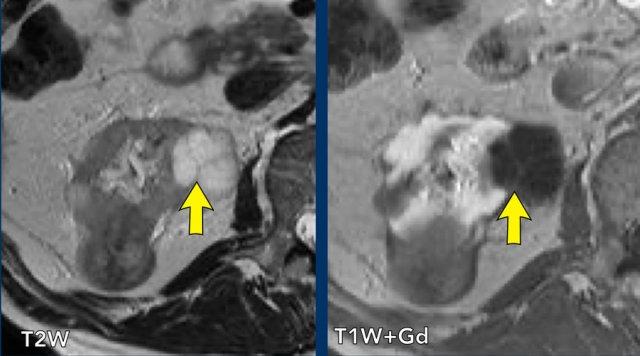

Trên hình ảnh chuỗi xung T2W, quan sát thấy một nang có 3 vách ngăn mỏng, nhẵn ở mặt trong của thận phải (mũi tên).

Dịch trong nang có cường độ tín hiệu T2W cao.

Trên hình ảnh chuỗi xung T1W sau tiêm Gadolinium, các vách ngăn có biểu hiện ngấm thuốc.

Tổn thương được phân loại là nang Bosniak II.

Không có chỉ định theo dõi.

Lưu ý rằng có một khối đặc thứ hai ở thận phía sau.